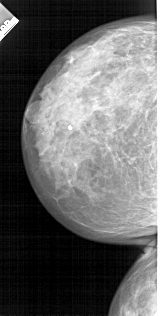

A_1713_1.LEFT_CC

LEFT_CC LINES 4726 PIXELS_PER_LINE 2386 BITS_PER_PIXEL 12 RESOLUTION 43.5 NON_OVERLAY